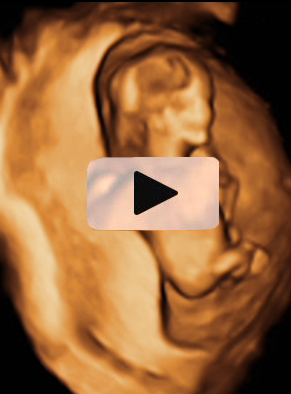

En la ecografía de la semana 12 de embarazo se distingue los genitales del feto, lo que permite saber con bastante probabilidad de acierto si se trata de una niña o un niño, como en este caso.

Cómo se ven los genitales de un feto varón de 12 semanas en la ecografía

Vemos en esta ecografía en dos dimensiones de un feto de 12 semanas. Si nos fijamos en la flecha, el tubérculo genital apunta hacia delante, lo que hace muy probable que el feto sea de sexo varón.